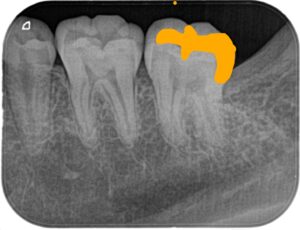

上のX線の患者さんは写真の左下の親知らず(正面から見て右下)が大きな虫歯になっており、手前の第二大臼歯もその影響で虫歯になっていました

赤い部分が虫歯です

一般的には第二大臼歯の咬合面から大きく削り、インレーと呼ばれる詰め物を作ると思います。下の写真のオレンジ色の部分を削るため、虫歯の部分1に対して健康な部分を2~3ぐらい削ります。